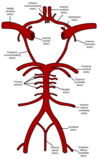

Foramen Magnum:Occupies central area of floor, transmits the medulla oblongata, the spinal portion of CNXI and the two vertebral arteries

Jugular foramen: CN IX, X & XI and sigmoid sinus (NB Sigmoid sinus becomes the internal jugular vein)

Internal acoustic meatus: Transmits the vestibulocochlear nerve and motor + sensory roots of the facial nerve.